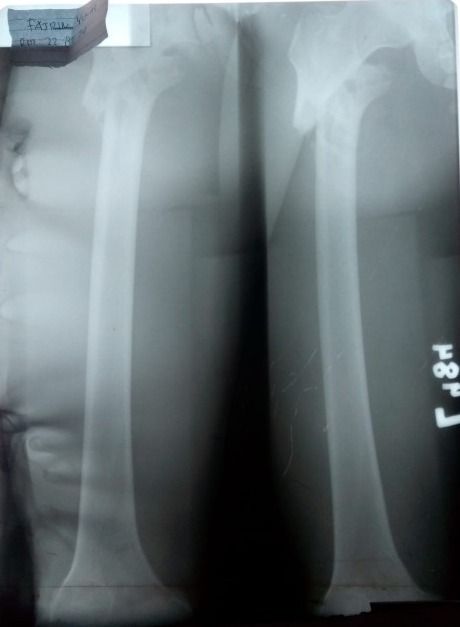

Tak ada yang menyangka, 16 Februari lalu Fajrin mengalami kecelakaan motor di Jl. Raya Padang Solok Panorama II. Saat itu hujan deras sehingga jalanan licin. Fajrin tak bisa mengendalikan motor saat turunan tajam dan tikungan hingga Fajrin terjatuh.

Kecelakaan itu mengakibatkan pinggul kirinya patah dan langsung dilarikan ke RS Reksodiwiryo Padang. Fajrin harus segera diobati.